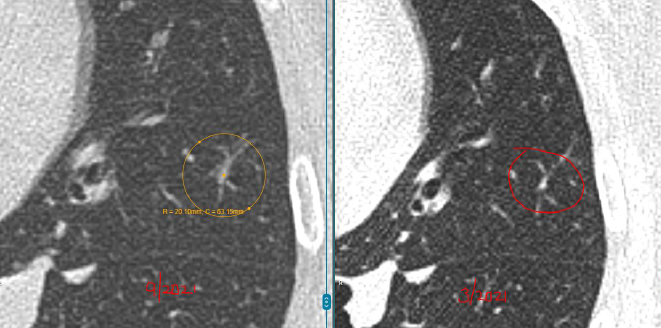

教授指出,右肺那颗4mm的磨玻璃结节虽然密度略有增加,但变化非常小,还不足以判断为恶化。

而左肺的两枚实性结节稳定了三年多,良性可能性超过99%。另外舌叶可见线状影,较前稳定,符合炎性、瘢痕特征。

“这些结节都太小,目前还不到该切的程度,继续观察很安全。”L教授说。他建议孙女士每年复查一次CT,不需要手术、不用活检。

- 大小和增长速度:超过8mm、短期内明显变大,才值得警惕。

- 形态特征:边缘毛糙、呈分叶状或伴随血管牵引的,恶性几率高。

- 时间稳定性:结节在2年以上没有变化,基本可以判定为良性。